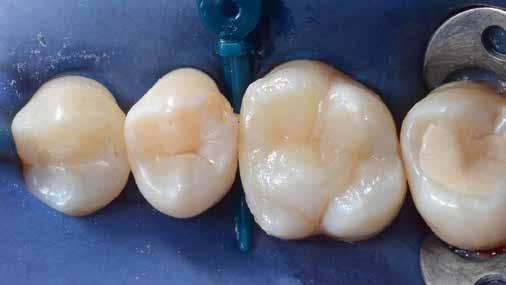

6. ábra: I. osztályú restaurációk az első moláris és a második premoláris fogakban. A széleken felesleges kompozit figyelhető meg (piros nyilak jelölik).

12. ábra: A premoláris fogak preoperatív állapota.

13. ábra: A premoláris fogak postoperatív fotója.